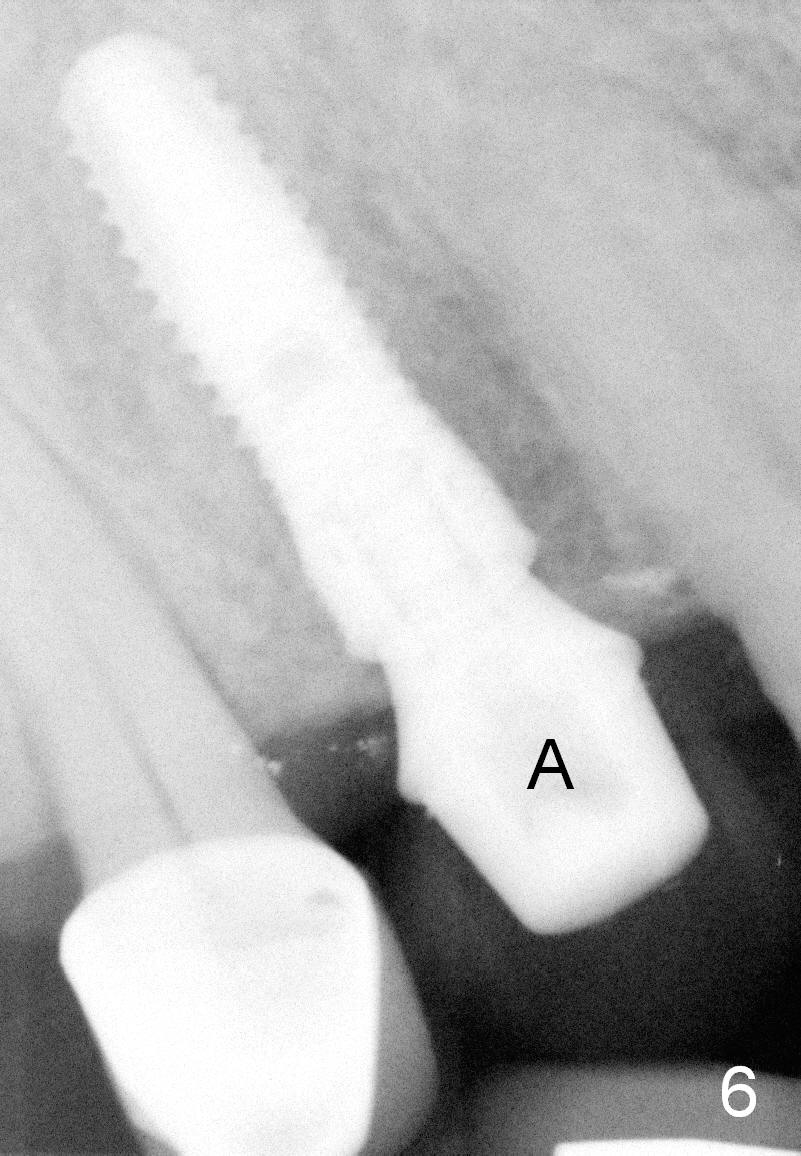

A 66-year-old man has lost several teeth (Fig.1,2). There is a particularly wide mesiodistal space for the site of #5 (Fig.1), probably due to distalization of the tooth #4 under heavy occlusion (Fig.2 arrow). A 4 mm tissue punch is used for access, followed by 1.6 mm pilot drill (Fig.3). After trajectory adjustment, a 2 mm parallel pin is inserted (Fig.4); later the osteotomy is moved distally (arrow). Finally a 4.5x14 mm implant is placed (Fig.5 I). Due to limited access, the implant is placed a little deeper than necessary; the gingival cuff of an abutment has to be longer (Fig.6 A: 5.8x4(3) mm). An immediate provisional is fabricated (Fig.7,8 P). The provisional looks wide (Fig.7). When the implant osteointegrates, limited orthodontic treatment will be done to idealize the space of #5 as follows.